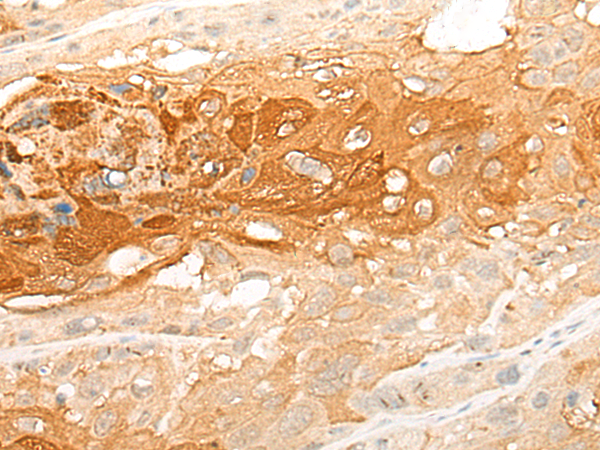

IHC Positive control: |

Human esophagus cancer; |

IHC Recommended dilution: |

30-150 |